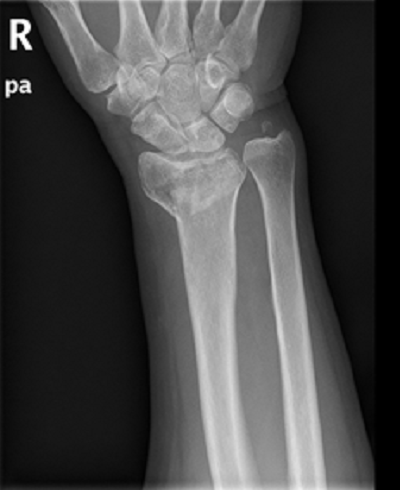

病例一:

诊断:桡骨极远端骨折。

治疗:内固定加外固定治疗。